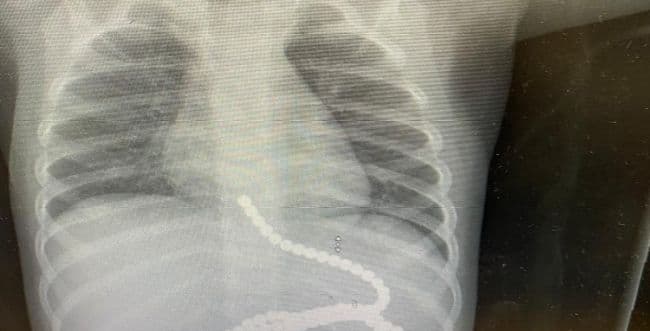

Upon his arrival, an X-ray was taken, which showed a large amount of magnets in the stomach and esophagus area.

Following this, the toddler underwent an endoscopy, during which most of the magnets were removed from his body. The operation was performed by Dr. Orit Elkayam, pediatric gastroenterologist and senior physician in the pediatric wing, in collaboration with the adult gastroenterology team led by Dr. Wissam Savit and Dr. Amir Shahin.

Dr. Nadav Slifer, director of the pediatric surgery department, who operated on the baby, said that during the operation, 11 additional magnets were found in different areas of the digestive tract, as well as holes in the stomach, small intestine, and large intestine, which were caused by the magnets penetrating the intestinal wall. When the magnets were removed, the surgeons repaired the holes.